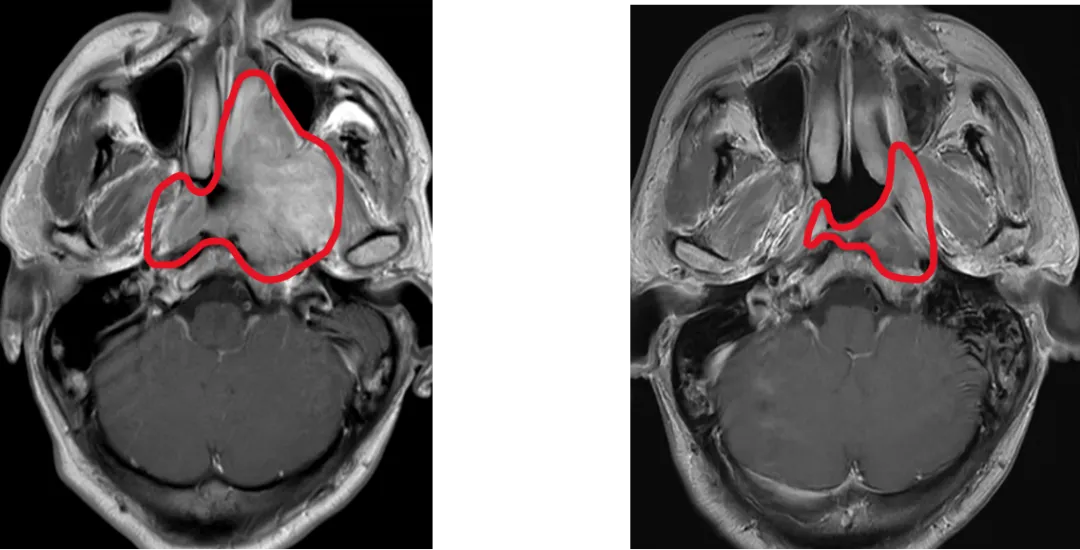

鼻咽癌高發(fā)于中國(guó),新發(fā)病例占全球47%。放射治療是鼻咽癌的根治手段,但中晚期患者需要在放療前接受化療,放療前化療使90%患者腫瘤縮小,而既往國(guó)際指南推薦放療照射范圍仍需包括化療前腫瘤大小覆蓋的范圍,導(dǎo)致周圍正常組織(如內(nèi)耳、腮腺)接受高劑量輻射,引發(fā)聽力損傷、口干等不可逆副作用,嚴(yán)重影響患者生活質(zhì)量。

為此,馬駿院士團(tuán)隊(duì)展開有關(guān)研究,采用了國(guó)際通用的標(biāo)準(zhǔn)多中心、隨機(jī)、平行對(duì)照設(shè)計(jì),納入445例中晚期鼻咽癌患者,隨機(jī)分為兩組:分別基于化療后和化療前腫瘤范圍進(jìn)行放療。主要終點(diǎn)為3年局部區(qū)域無復(fù)發(fā)生存率,次要終點(diǎn)包括毒副反應(yīng)和生活質(zhì)量。

這項(xiàng)多中心III期臨床試驗(yàn)證實(shí),僅照射化療后的腫瘤范圍,并沒有增加復(fù)發(fā),卻顯著降低了毒副反應(yīng),顯著改善患者生活質(zhì)量,使我國(guó)鼻咽癌診療實(shí)現(xiàn)從“保生存”到“優(yōu)生存”的跨越式突破。3年局部區(qū)域無復(fù)發(fā)生存率達(dá)91.5%(與傳統(tǒng)療法持平);嚴(yán)重放射性口腔黏膜炎降低4成,晚期嚴(yán)重中耳炎發(fā)生率銳減5成,口干癥狀改善6成;整體健康狀態(tài)、體力狀態(tài)、情緒功能顯著改善,口干及唾液黏稠癥狀減輕。